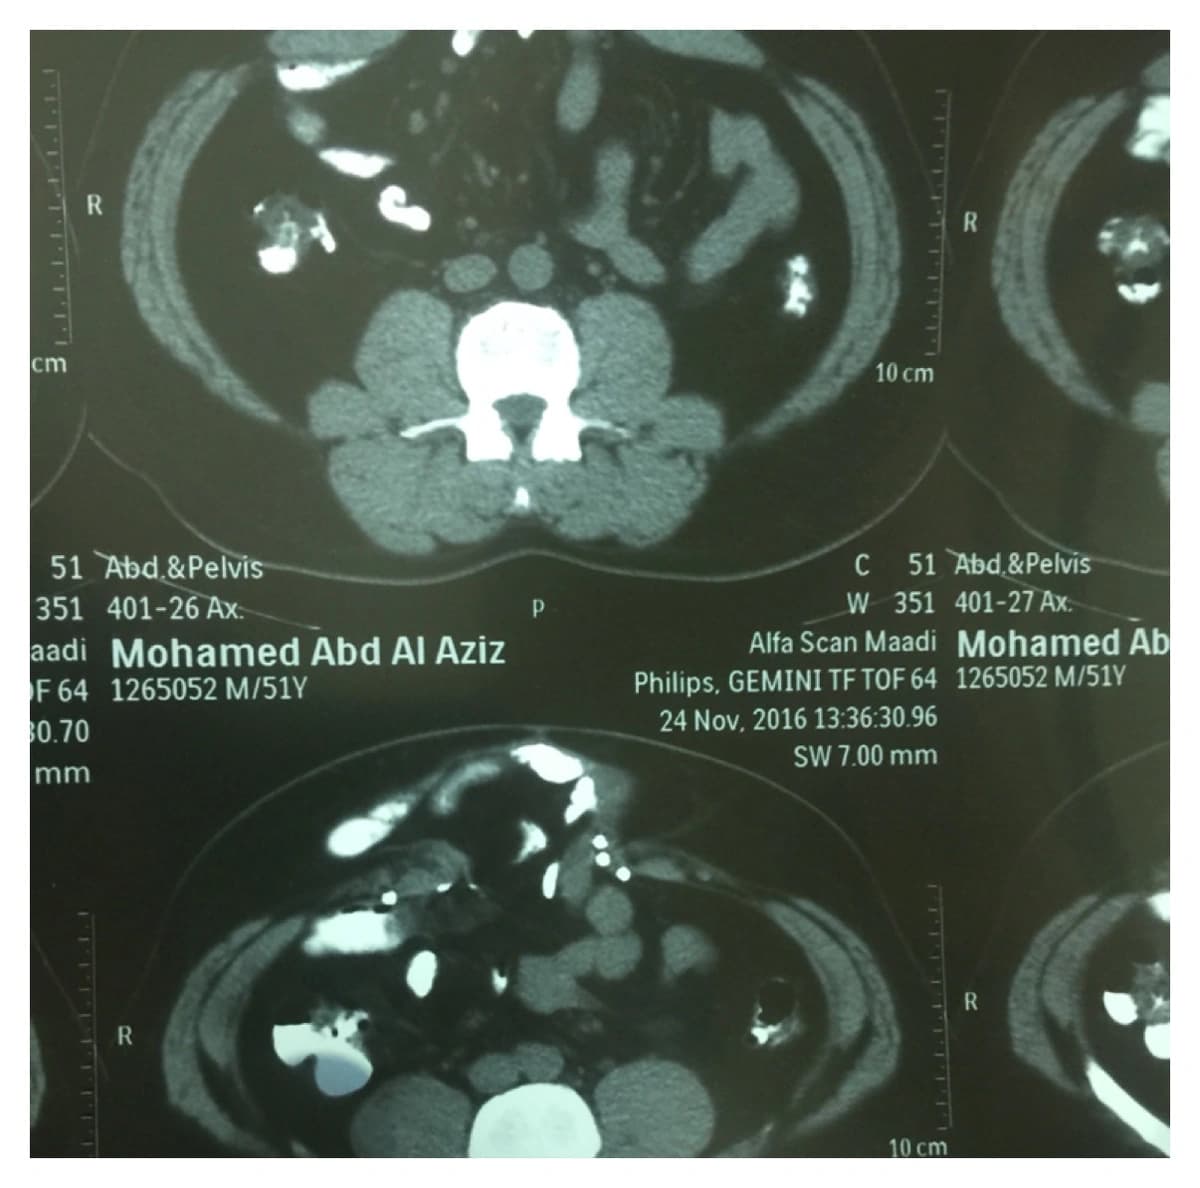

وأضاف رئيس الفريق الطبي، أنه تمّت الموافقة على إجراء العملية بعد دراسة وضع المريض الصحي بشكل جيد، وبالصور المقطعية، وبحمد الله، أجريت العملية على ثلاث مراحل؛ الأولى تمثلت في إغلاق من داخل البطن؛ حيث وضعت شبكة جراحية مخصصة لذلك، وهي الخطوة التي اعتبرت كافية لإصلاح الفتق. ثم المرحلة الثانية، وكانت الأصعب، وهي فصل مكونات جدار البطن، ثم إعادة تشكيلها لإغلاق فتحة جدار البطن. وأخيرًا المرحلة الثالثة، وهي تثبيت جدار البطن من الخارج بوضع شبكة. مؤكدًا نجاح العملية وتماثل المريض للشفاء.